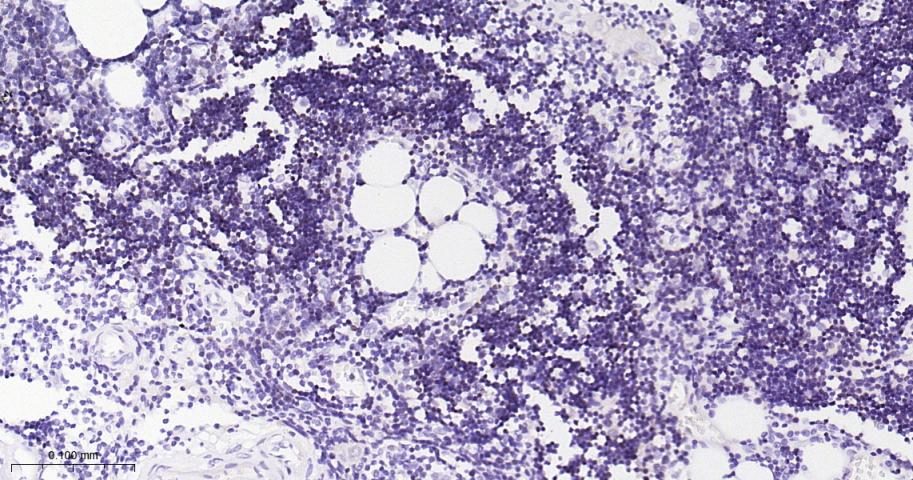

Paraformaldehyde-fixed, paraffin embedded Human Thymus; Antigen retrieval by boiling in sodium citrate buffer (pH6.0) for 15 min; The section was incubated with DNTT Monoclonal Antibody, Unconjugated (bsm-61808R) at 1:200 overnight at 4°C, followed by conjugation to the bs-0295G-HRP and DAB (C-0010) staining.